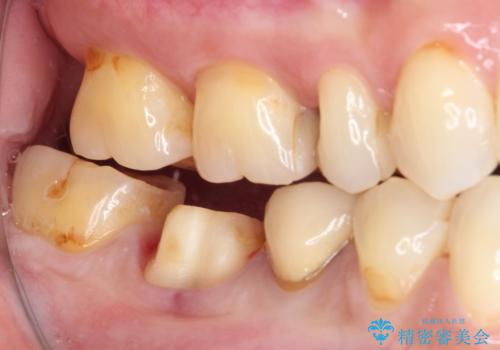

奥歯が欠けてしまった オールセラミッククラウンによる補綴治療

- 奥歯が欠けてしまった事を主訴として来院した患者様です。

頬側の欠けている範囲が大きく、以前治療した詰め物も大きいため、詰め物を外してむし歯を除去し、

形を整えて一度仮歯に置き換え、フルジルコニアクラウンにて補綴しました。

高強度のフルジルコニアクラウンは、強いかみ合わせでも壊れにくいです。

また審美的にも満足していただけました。